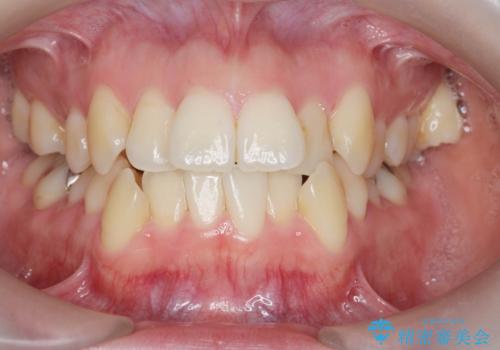

[ マウスピース矯正 ] がたがたした歯並びを治したい

担当医 大元洋佑